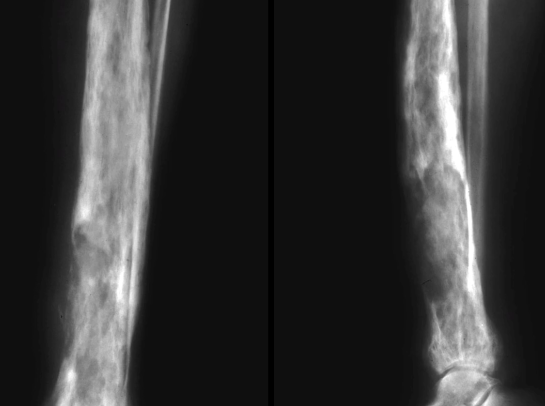

Phase Active Lytique

- Lyse craniale

- Lyse des os longs en “brin d’herbe”

- Les lyses sont bien délimitées, avec une fin en “V”

Bassin et Membres

- Epaississement des lignes du bassin

- Epaissisement Coricla + Trabéculaire

Bowing